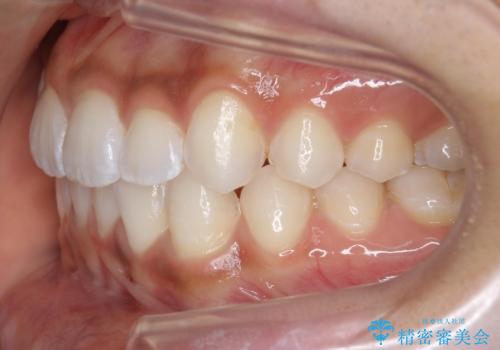

前歯のがたつき 1年かからず治療 マウスピース矯正

- 前歯のがたつきを主訴に来院。

インビザラインで歯を抜かずに並べました。

マウスピースの延長(リファインメント)もなく、短期間で綺麗に並びました。